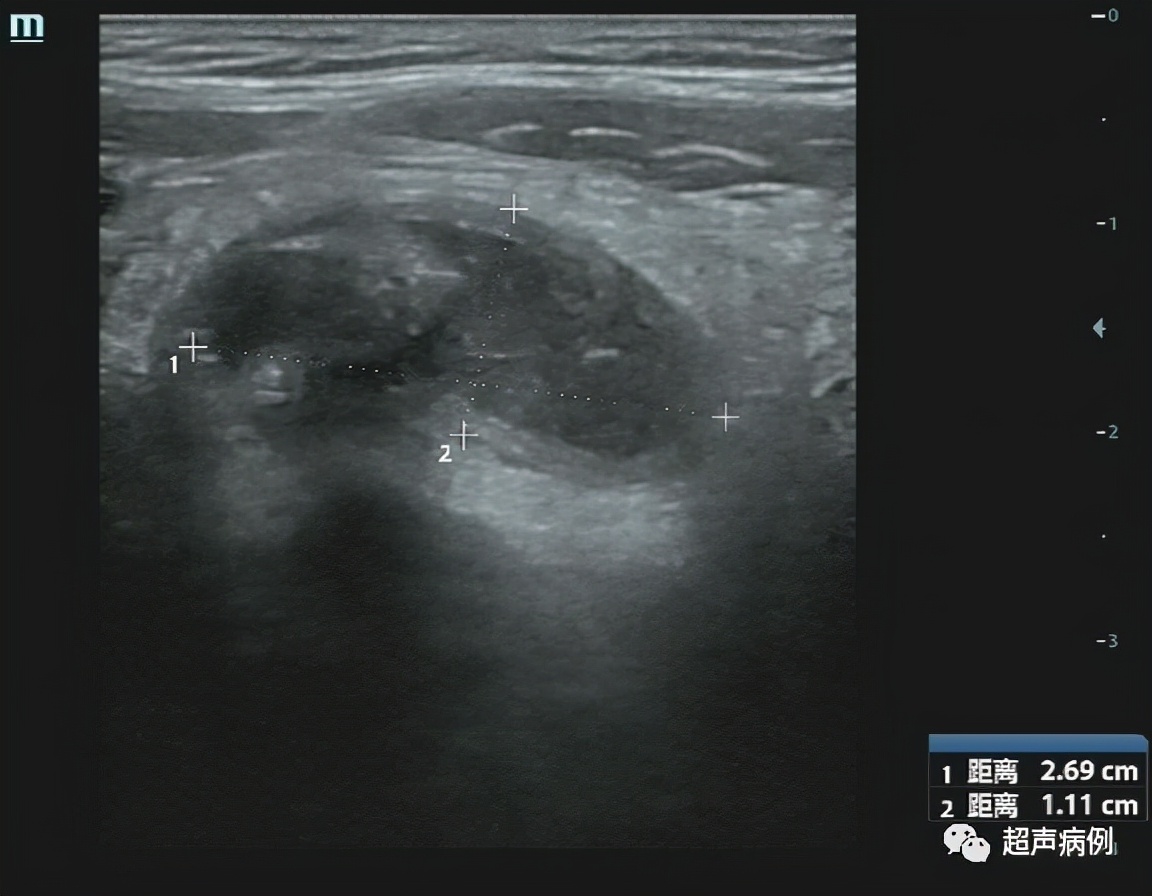

病例5

男,70岁,转移性右下腹痛3天。

超声检查:

在右下腹阑尾解剖区查见管状弱回声,范围约3.0×0.88cm,周围组织回声增强,CDFI:边壁可见点状血流信号。

病理诊断:急性化脓性阑尾炎及其周围炎。